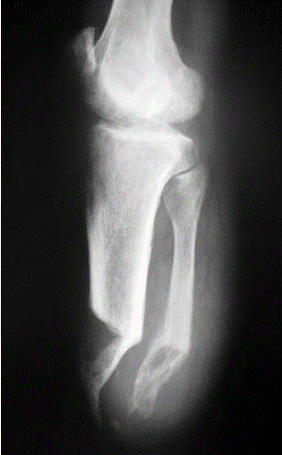

# Amputações - Na amputação transtibial, qual técnica operatória diminui a instabilidade tibiofibular proximal e proporciona um coto mais estável?

- **Sinostose tibiofibular distal (técnica de Ertl)**

29

# Amputações - Dentro das amputações do pé, qual é a mais comum?